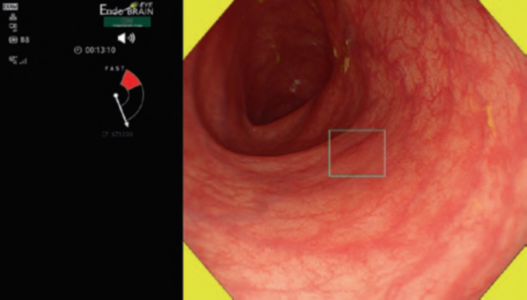

The working group members carried out a systematic review of the English literature to determine widely accepted diagnostic systems. Consequently, the best-accepted diagnostic system was proven to be the VS classification system. Based on this system, MESDA-G was constructed using an evidence-based approach (. Figs. 3, 4, 5, and 6) [2]. First, lesions suspicious for EGC should be detected by careful inspection using conventional white-light endoscopy. Subsequently, magnified observations should be performed. Owing to the high sensitivity of the demarcation line [8], if it is absent, the suspicious lesion is diagnosed as noncancerous (. Fig. 4a, b). However, if the demarcation line is present, further assessment is required to determine the presence of an irregular MV or MS pattern. If an irregular MV and/or MS pattern is detected, the suspicious lesion is diagnosed as cancerous (. Fig. 6a, b) [1, 5, 6, 8]. If both the irregular MV and MS patterns are absent, the tumor is diagnosed as noncancerous (. Fig. 5a, b) [1, 5, 6, 8].